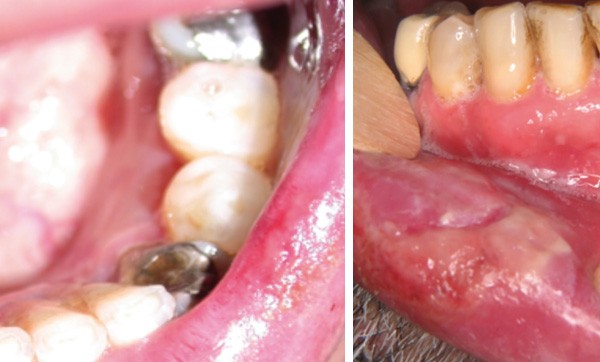

CAS 1

Motif de la consultation. Patient de 55 ans venu consulter pour l’apparition d’une ulcération de la lèvre inférieure douloureuse.

Histoire de la maladie. La lésion était présente depuis deux mois. Son volume avait tendance à augmenter.

Interrogatoire. Il mettait en évidence un antécédent de leucémie aiguë myéloïde ayant échappé à toutes les lignes de chimiothérapie et thérapie ciblées. Le patient avait subi une allogreffe de moelle osseuse un an auparavant. Cette allogreffe s’était compliquée d’une maladie du greffon contre l’hôte (GVH) chronique avec une atteinte cutanée sclérodermiforme. Le patient prenait une prophylaxie anti-infectieuse et 0,25 mg/kg de prednisolone associée à de la ciclosporine à la dose de 60 mg le matin et 60 mg le soir. Depuis deux mois, il avait remarqué une xérostomie et l’apparition d’une ulcération douloureuse de la lèvre inférieure qui avait tendance à s’étendre.

Examen clinique. Il révélait une ulcération de 2 cm de grand axe, à cheval entre la muqueuse labiale et le bord vermillon. L’ulcération était profonde, recouverte d’un enduit fibrineux humide et de quelques croûtes plus ou moins impétiginisées. L’examen intrabuccal montrait des lésions kératosiques lichénoïdes en réseau et en plaque.